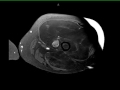

42-year-old male with gradually enlarging left thigh mass. Images demonstrate a multiseptated T1 hyperintense, STIR hypointense, heterogeneously enhancing mass enveloping the left femoral diaphysis and extending into the surrounding soft tissues. No periosteal reaction. There are enhancing, wispy, septations on the postcontrast images with more nodular excrescences at the inferior most aspect of the mass. On resection, this lesion was found to be a well-differentiated liposarcoma, which represents the second most common soft tissue sarcoma. Liposarcoma typically arise in adults between the ages of the 40 and 60 years. Typical locations include the extremities or retroperitoneum. Well-differentiated liposarcoma is the most common subtype, occurring in greater than 50% of cases. Extremity liposarcomas are typically slow growing and have variable rates of localized disease recurrence with deeper lesions more likely to recur. Primary surgical treatment is with wide local excision.